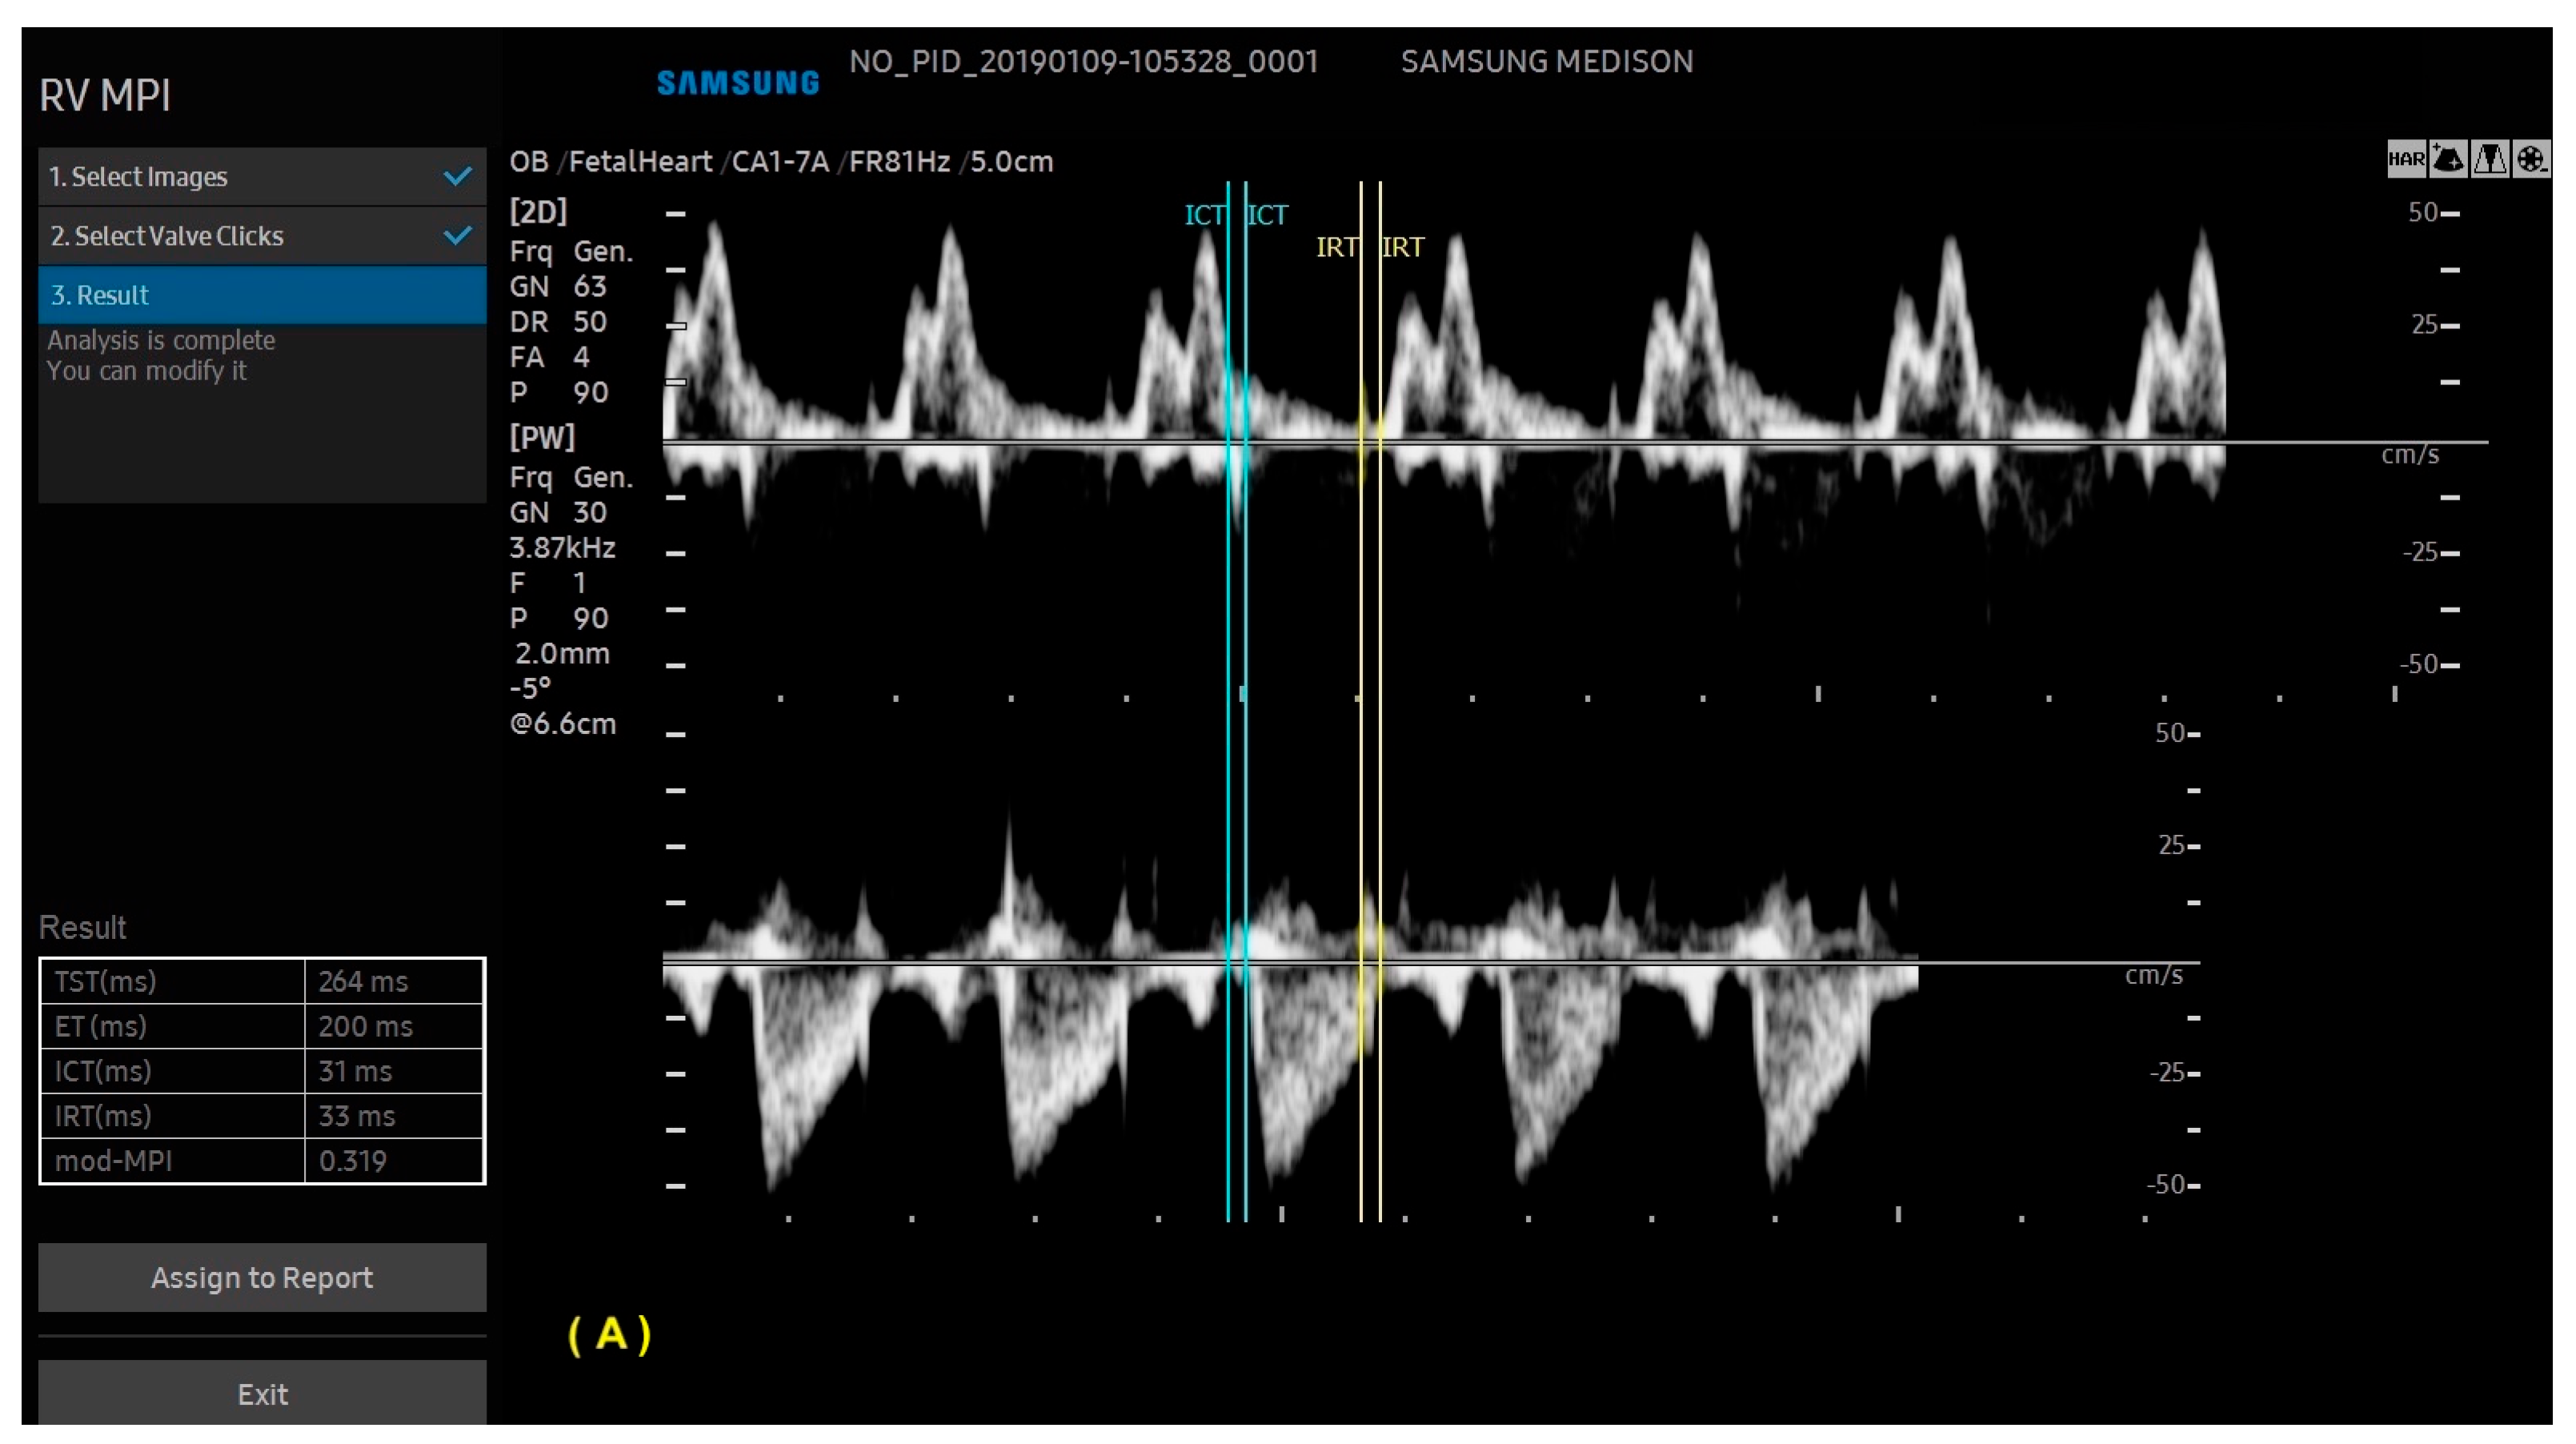

- Scharf, J.L.; Dracopoulos, C.; Gembicki, M.; Welp, A.; Weichert, J. How Automated Techniques Ease Functional Assessment of the Fetal Heart: Applicability of MPI+™ for Direct Quantification of the Modified Myocardial Performance Index. Diagnostics 2023, 13, 1705. [Google Scholar] [CrossRef] [PubMed]